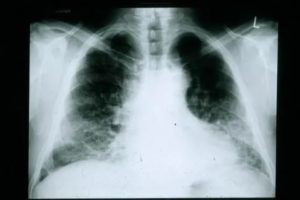

Визуально после пневмонии он определяется на рентгеновских снимках в виде фиброзных тяжей и рубцов – полосы затемнения. Это приводит к уменьшению дыхательной поверхности легких и развитию хронической дыхательной недостаточности.

Фиброзные тяжи на рентгеновском снимке